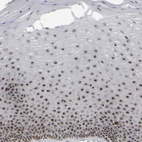

Immunohistochemical staining of human skeletal muscle shows strong positivity in nucleoli in myocytes.